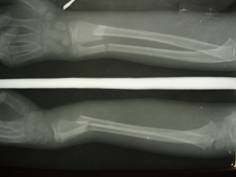

Descriptio roentgenogrammatum cum schemate

На рентгенограмі – перелом кісток лівого передпліччя в н/3 зі зміщенням уламків.

Мал.1.

Рентгенограма кісток предпліччя при переломі обох кісток предпліччя (пряма проекція).